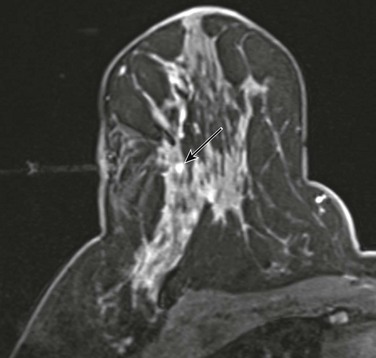

Magnetic resonance imaging (MRI) is helpful in evaluating the extent of disease with ILC, showing more extensive disease than does mammography in 39% of cases. A cautionary note—ILC may show only faint enhancement with progressive kinetics on MRI. The washout pattern is much less common for ILC than IDC. Remember—when interpreting breast MRI and deciding on your management recommendation, the morphologic appearance always trumps the curve.

CASE 11-1. A 62-year-old woman with screening MRI. What is the most likely diagnosis of the left breast mass?

CASE 11-1. This is suspicious for a mucinous carcinoma. The mass is hyperintense on T2, but has heterogeneous enhancement and ill-defined margins. This should not be mistaken for a fibroadenoma.